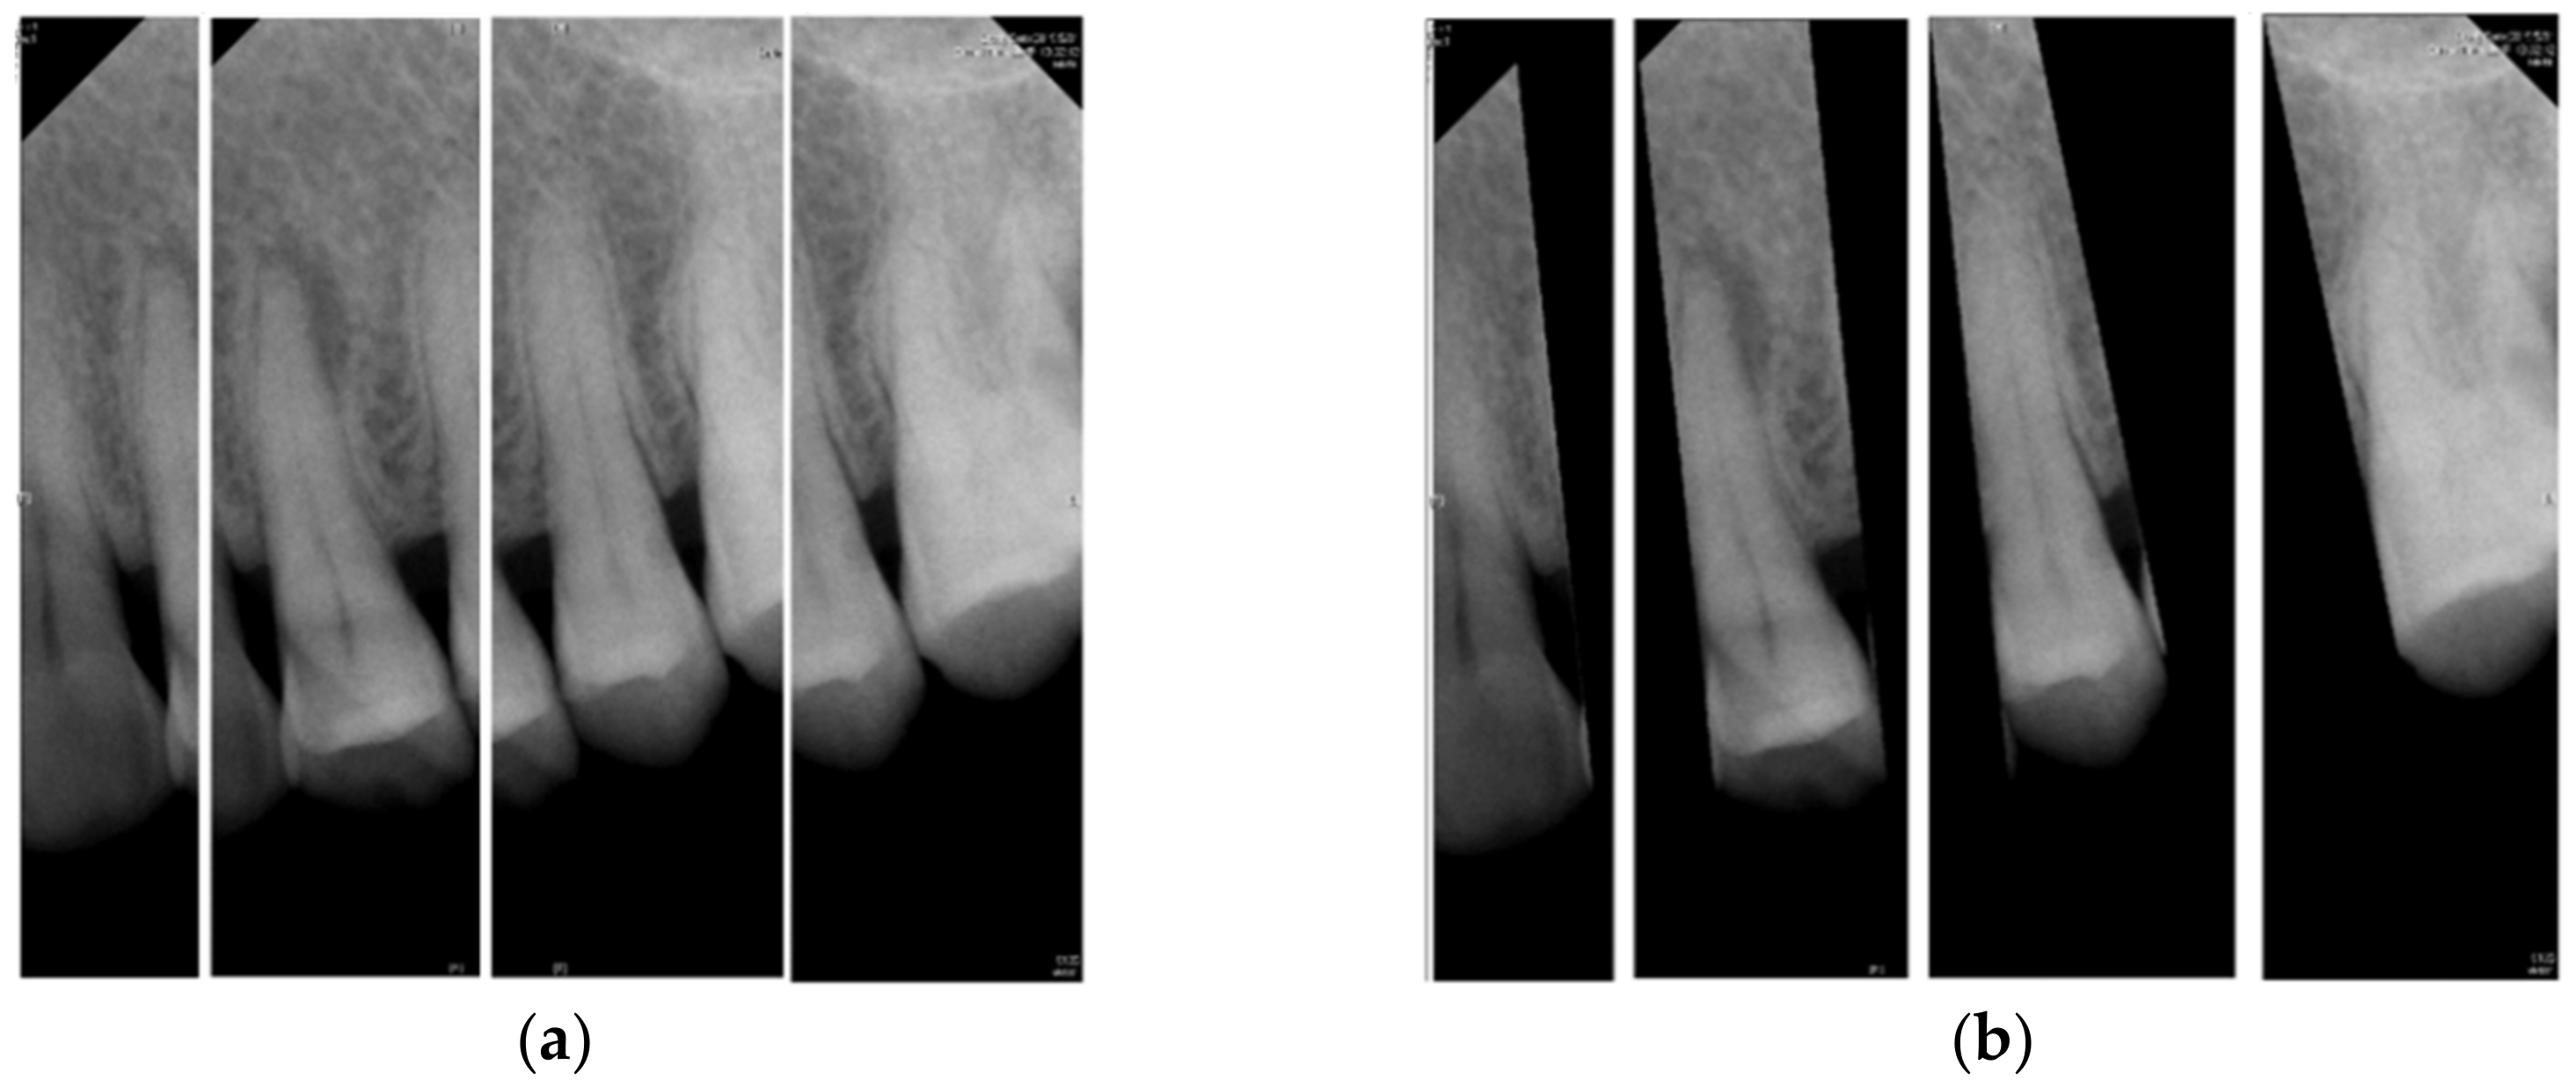

- In the image cropping preprocessing part, this study adds the adaptive threshold and angle rotation technology. Compared with the existing methods, this method significantly improves the image clarity and accuracy of a single tooth image.

- This study proposes an advanced image enhancement technique for apical lesions. It adds raw grayscale images and Gaussian high-pass filtered images to highlight the possible lesion areas and changes the color of the possible lesion area to green. Experiments show that the accuracy of the model is improved by more than 10% which proves that the proposed method is intuitive and effective.

- The innovation of this work is to realize the classification of various diseases. It can simultaneously judge a variety of different types of dental diseases (such as apical lesions, fillings, etc.), and the obtained final accuracy of the model proposed in this paper is as high as 93%. AlexNet even improves the accuracy up to 96.21% which is 4% higher than the state-of-the-art in [23].

2. Materials and Methods

2.3. Image Identification

2.3.1. CNN Model

2.3.2. Adjust Hyperparameter

3. Results

4. Discussion

5. Conclusions